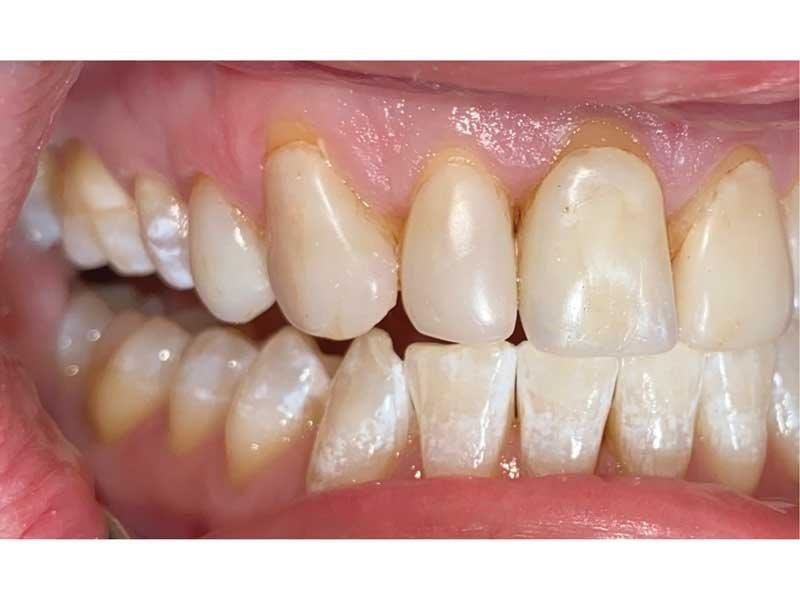

Meet Lorraine, who came into my office to “redo her bonding.” Lorraine had some upper anterior teeth done years ago with resin, which now was dull, stained and breaking down (Figs. 1–3). She had an amount of money in mind that she thought it would cost. She was very wrong.

Fig. 1

Fig. 2